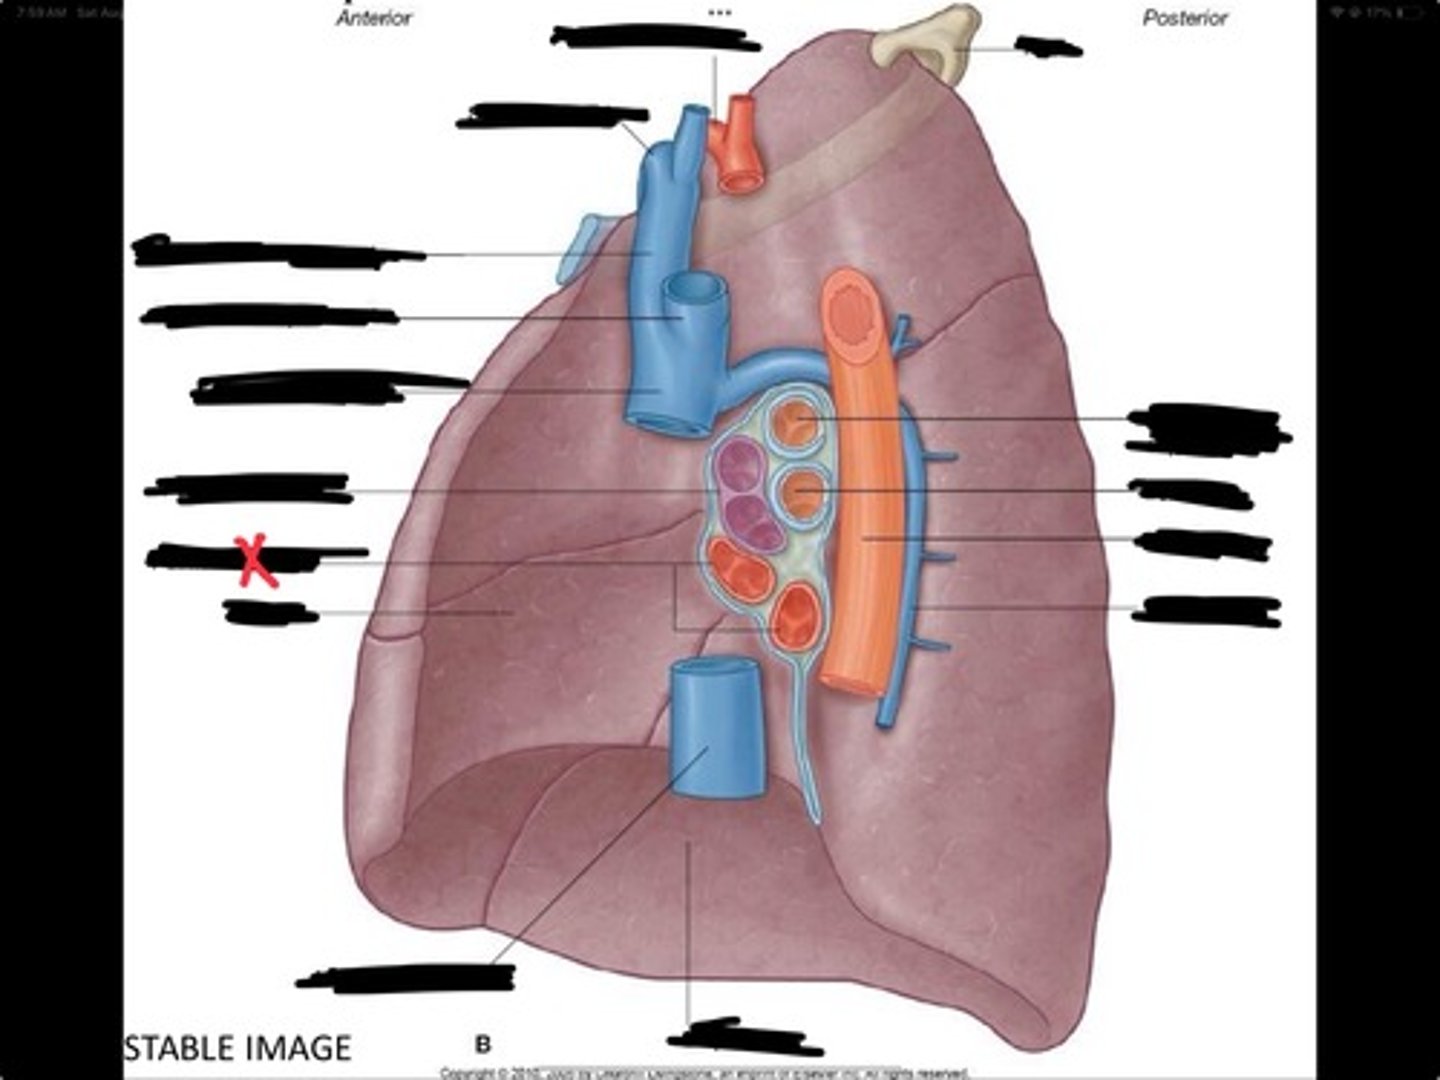

Superior vena cava

Subclavian vein

Right bracheocephalic vein

Subclavian artery

Esophagus

Bronchus

Rib 1

Left subclavian artery

Left brachiocephalic vein

Aortic arch

Pulmonary artery

Pulmonary vein

Heart

Left brachiocephalic vein

Azygos vein

Esophagus

Bronchus

Fibrous pericardium

Parietal layer of serous pericardium

Pericardial cavity

Visceral layer of serous pericardium

Junction between fibrous pericardium and adventitia

Heart

Thoracic aorta

Rib 1

Pulmonary artery

Bronchus to superior lobe